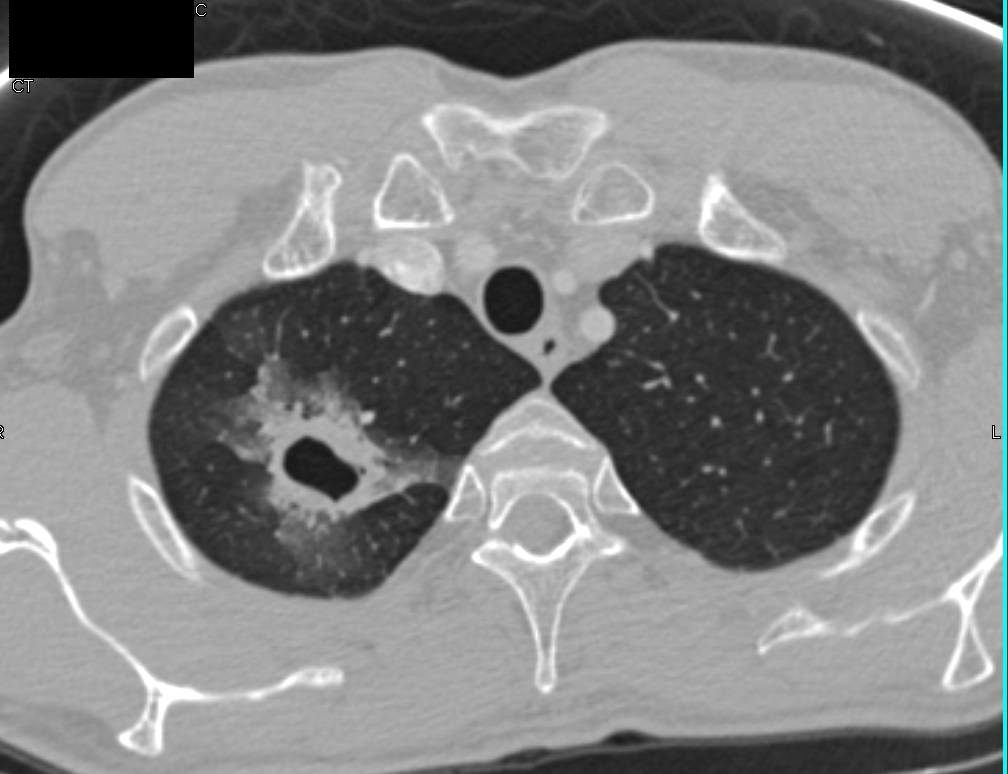

From www.ctisus.com

Cavitary Lesion due to Probable MAI Infection Chest Case Studies What Causes Mai Lung Disease You’ll most likely need treatment for a year or more to. Mac is often hard to get rid of. Treatment of nontuberculous mycobacterial (ntm) infection of the lung is dependent upon a number of factors, including the. Mac lung disease is an infection caused a group of bacteria called mycobacterium avium complex (mac). However, in north america, most mycobacterial lung. What Causes Mai Lung Disease.